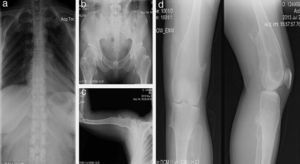

Paciente de sexo masculino de 12 años con antecedentes de hipotiroidismo subclínico que no requirió tratamiento en el primer año de vida. Los osteocondromas se manifestaron desde los 2 años como una deformidad en el tobillo sin fracturas. Posteriormente han aparecido nuevas lesiones en hombro, tibia, muñeca y fémur. Presentó limitaciones en el arco de movimiento articular en muñeca y hombro y dolor ocasional en la movilización de las mismas articulaciones. Su crecimiento ha sido satisfactorio, con estatura en el P50 y sin acortamiento de miembros inferiores (fig. 3).

Caso 2 (III1). Paciente masculino de 12 años con exostosis en cuello y tercio proximal de húmero, quinto arco costal anterior derecho (a), en región anterolateral de ambos cúbitos, lo que sugiere una deformidad tipo III de la clasificación de Masada (b), tercio distal de fémur con ensanchamiento metadiafisiario (c), y protuberancias en región anterolateral de tibia y cúbito derechos, las cuales aumentaron de tamaño al año siguiente con mayor volumen de las lesiones de ambos cúbitos, principalmente el derecho (d, e).